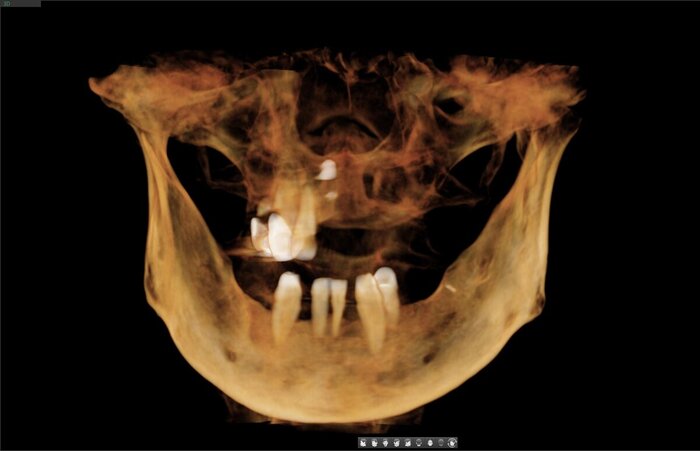

Зубы:

Протезы

Получилось так, что сверху всего 8 зубов, по 4 с каждой стороны. Чёрная точка (которую вы точно увидите, скос эмали на зубе 1.1) - конструктивные особенности, всё это будет закрыто пломбировочным материалом. Зуб 1.1 - дополнительный имлантат, который потом планируем убрать. Он нужен лишь для усиления, ибо торк полноценный был получен только на одном из остальных 6-ти установленных.

Напоминаю - протезы временные адаптационные

Так же важный момент - верхний протез соприкасается с нижним только в точках полученного торка (их всего 2), остальное "на весу" и жевать не способно.

Рекомендации - мягкая, жидкая пища 4 месяца! Это важно.

Низ - всё ок.